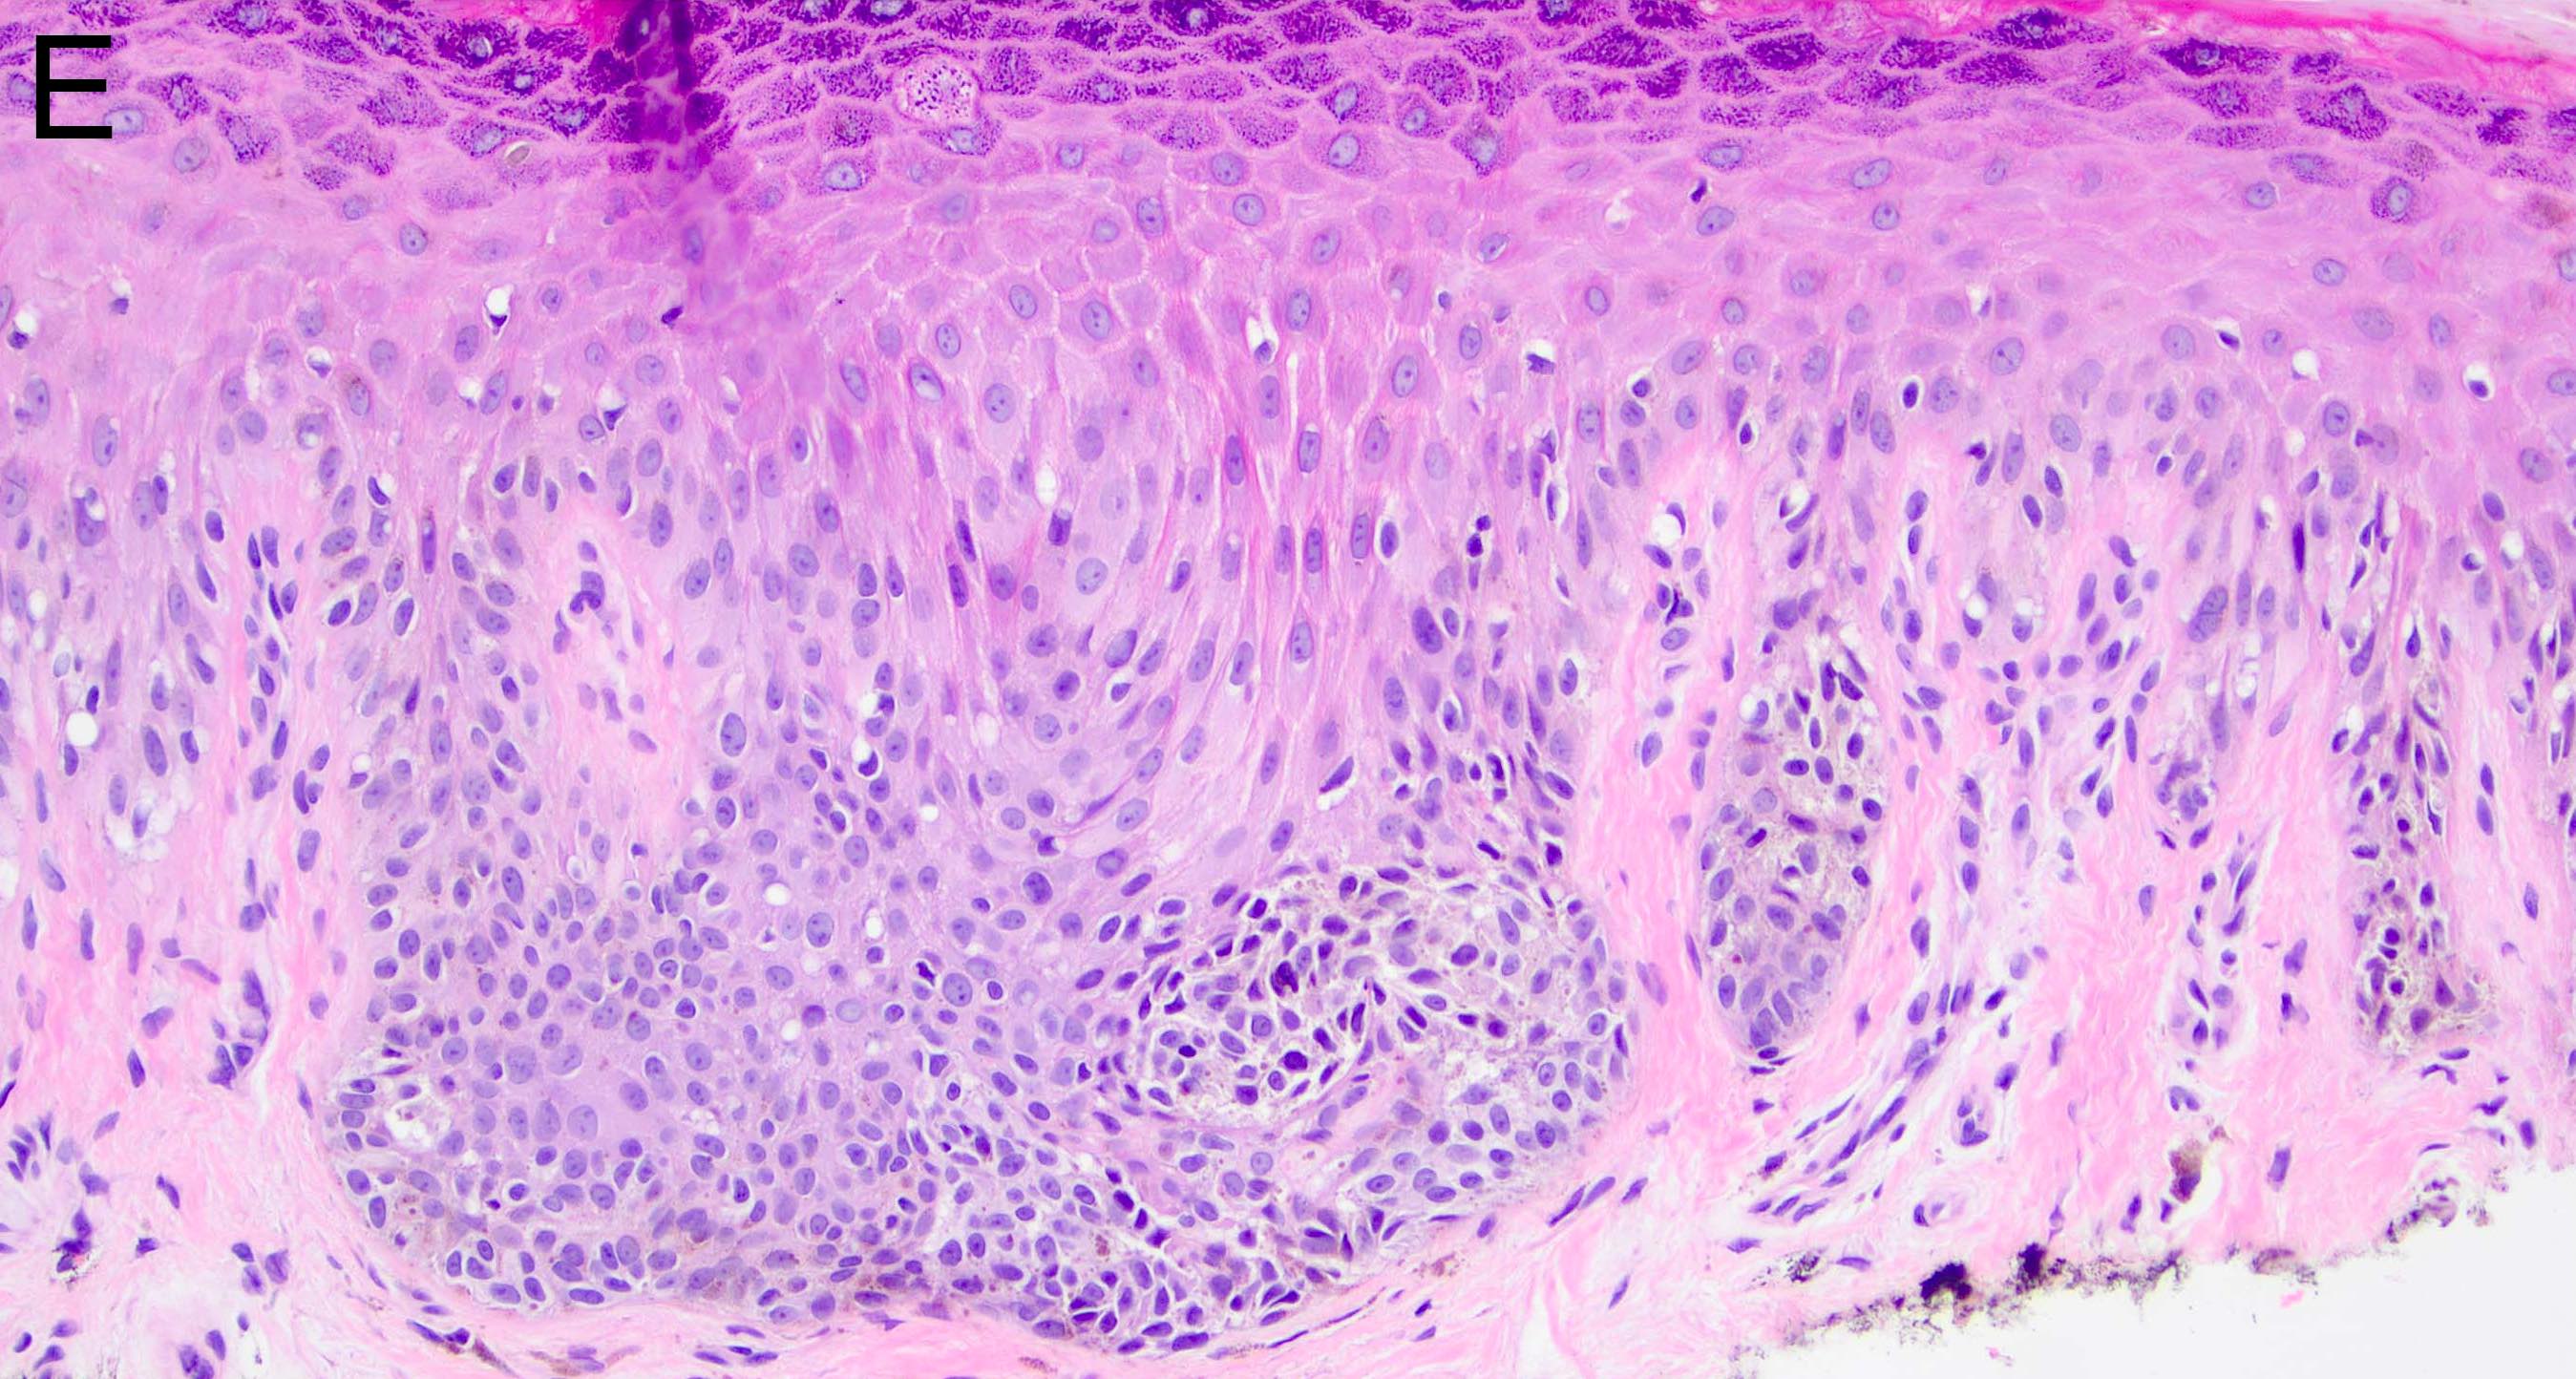

Microscopic (histologic) images

- Melanocytic nevi of the acral skin (Am J Dermatopathol 2016;38:867):

- May have unusually prominent pagetoid or lentiginous growth pattern

- Should not display high grade cytologic atypia

- Dermal component should display well formed nests and maturation with descent

- Cytologic atypia and mitotic activity should not be seen in dermal component

- There is an absence of lentiginous involvement of the crista profunda intermedia

- Banal appearing nests along eccrine apparatus are an acceptable feature in acral nevi